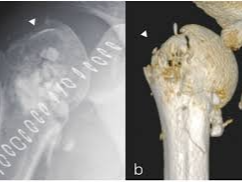

어깨 주변 골절은 단순히 뼈가 붙는 시간만으로 설명하기 어려운 손상입니다. 많은 분들이 “어깨뼈 골절 통증기간이 얼마나 되나”, “상완골 골절로 수술하면 입원을 며칠이나 하나”를 가장 먼저 궁금해하시지만, 실제 임상에서는 골절 부위가 견갑골인지, 상완골 근위부인지, 골절선이 단순한지 분쇄형인지, 수술을 했는지, 다른 장기나 뼈의 동반 손상이 있는지에 따라 통증과 회복 곡선이 크게 달라집니다. 특히 어깨는 관절 가동범위가 넓은 대신 한번 다치면 강직이 쉽게 생기는 부위라서, 통증이 줄어드는 시점과 일상 기능이 회복되는 시점이 서로 다를 수 있습니다.

일반적으로 어깨 주변 골절은 뼈가 붙는 데 약 6주에서 12주 정도가 걸리고, 실제 움직임과 근력 회복은 수개월 더 이어질 수 있습니다. 견갑골 골절은 다수에서 보존적 치료가 가능하지만, 상완골 특히 근위 상완골 골절은 변위 정도에 따라 고정술이나 인공관절수술까지 고려되기도 합니다. 따라서 통증기간만 단정적으로 묻기보다, 골절의 형태와 치료방식을 함께 이해하는 것이 현실적입니다.